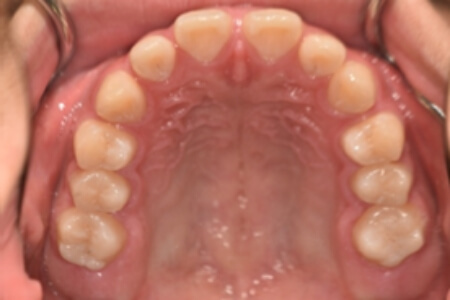

初診時

症例 症例 症例 症例 症例

治療内容の詳細 初診時16歳の男性で、前歯のすきまを気にされ、来院されました。

検査の結果、アングルⅢ級不正咬合と診断しました。